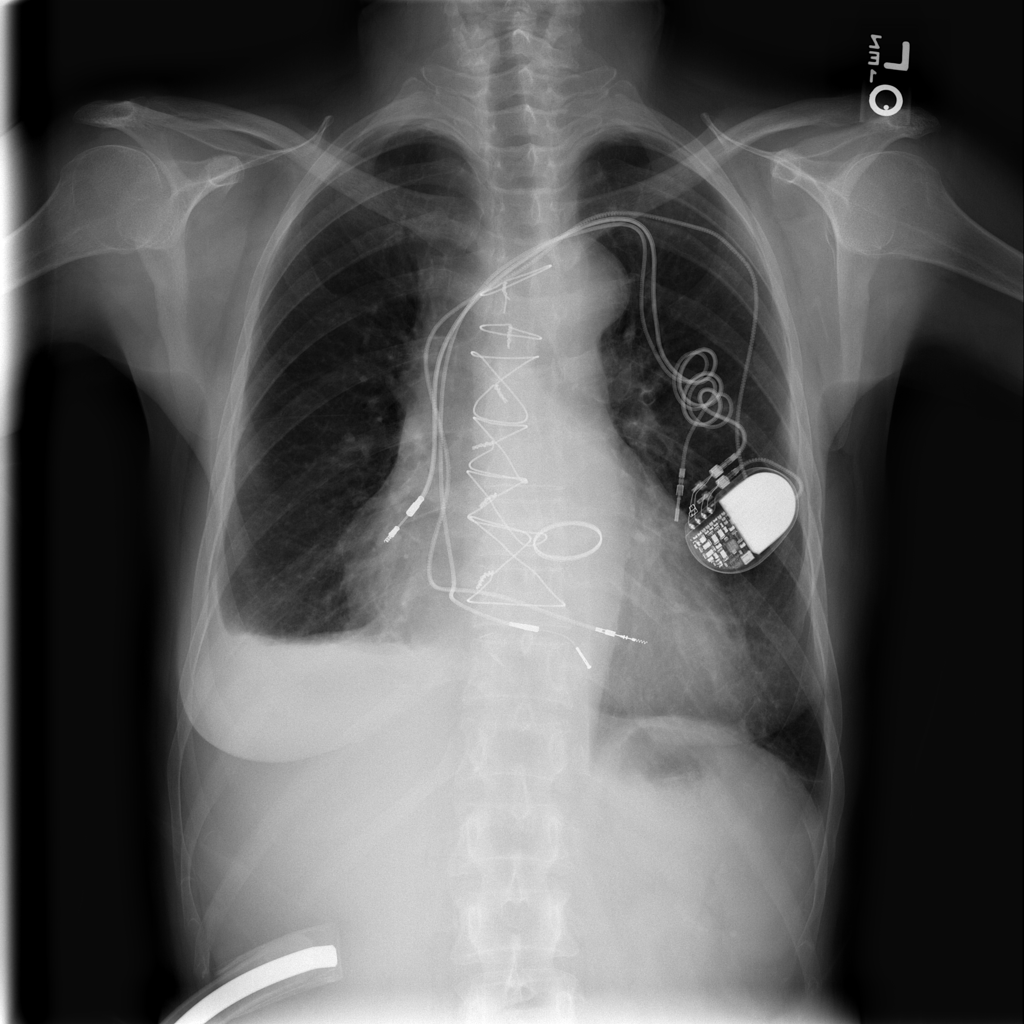

PAT-F3E7 · IMG-000Cardiomegaly

PAT-F3E7 · IMG-000

PA